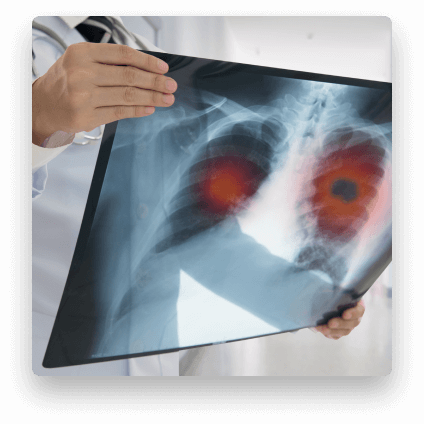

Lung CT Scan

A lung CT scan offers superior visibility compared to traditional x-rays, making it an essential non-invasive diagnostic tool. These scans can:

• Provide detailed images of lung tissue

• Identify lung cancer at early stages

• Detect various lung conditions without invasive procedures

• Monitor lung health with greater precision